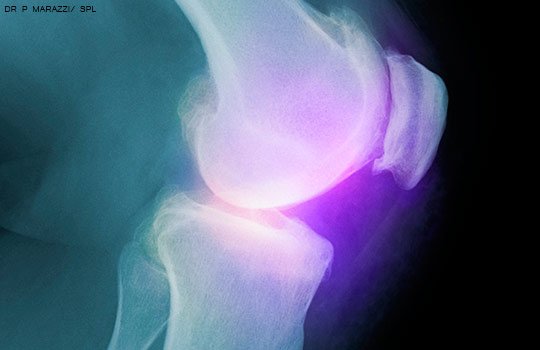

Una guía de práctica clínica desaconseja la cirugía artroscópica para la artritis degenerativa de la rodilla y los desgarros meniscales. BMJ, 10 de mayo de 2017

Corticoides intraarticulares: sin eficacia en la artrosis de rodilla

El uso regular de triamcinolona favoreció la pérdida de volumen del cartílago sin mejoría significativa en las escalas de dolor. JAMA, 16 de mayo de 2017